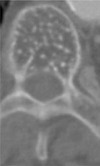

Artritis reumatoide

- Reconstrucción sagital de TAC

- Erosiones en odontoides y arco anterior de C1 con subluxación anterior C1-C2.

Artritis reumatoide

- Erosiones y pinzamiento en articulaciones interapofisarias

Artritis reumatoide

- Reconstrucción coronal de TAC

- Erosiones y esclerosis en la articulación C1-C2 derecha

Artritis reumatoide

- Reconstrucción sagital de TAC

- Afectación de la columna cervical (erosiones, esclerosis, destrucción discal) con impresión basilar

Artritis reumatoide

- Reconstrucción sagital de TAC

- Erosiones y esclerosis en la articulación C1-C2 de un lado